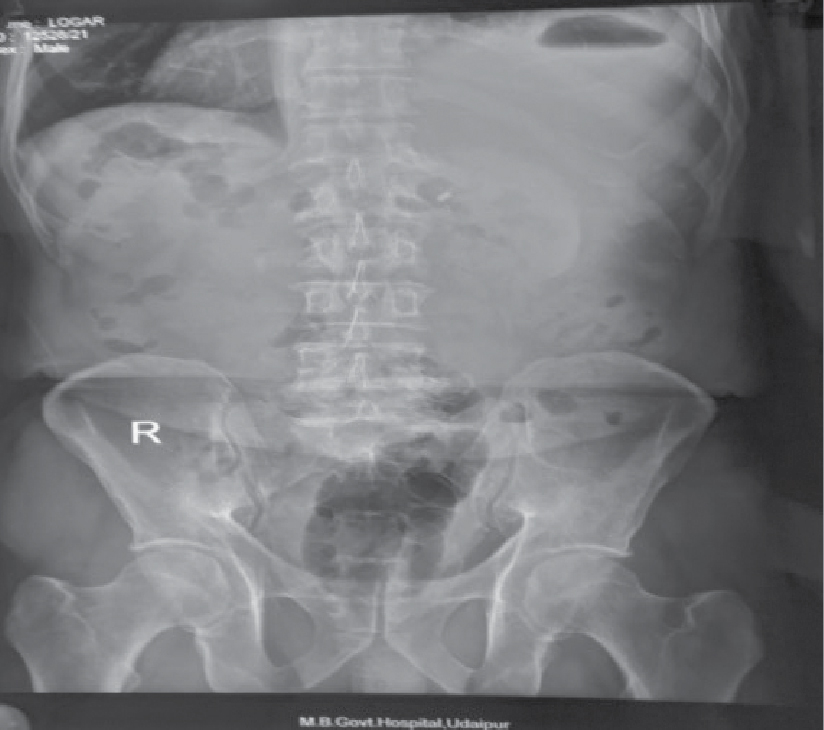

On examination, patient was febrile and abdominal tenderness was present over right hypochondrium; bowel sounds were present. His pulse rate was 110/min, blood pressure was 110/70 mmHg and respiratory rate was 20/min. Investigations done were as follows: Hemoglobin - 7.3 g/dL, total white blood cell count - 6900/cc, neutrophil - 50% and lymphocytes - 19.2%. His total bilirubin and direct bilirubin were normal. Serum glutamic oxaloacetic transaminase (SGOT), serum glutamic pyruvic transaminase (SGPT) and alkaline phosphatase (ALP) were increased around 10 times. His total protein and albumin were below normal. Chest X-ray and X-ray flat plate abdomen (FPA) in erect posture showed gas shadow under right hemidiaphragm (Figs. 1 and 2).

Figure 2. X-ray abdomen erect shows gas under right hemidiaphragm.

The chest X-ray and X-ray FPA are abnormal in approximately 50% of the cases, with findings reflecting subdiaphragmatic pathology, such as an elevated right hemidiaphragm, right pleural effusion or atelectasis. Occasionally, there may be left-sided findings in the case of an abscess in the left lobe of the liver.

In this case, liver abscess filled with pus and having air fluid level visible in CECT abdomen, was responsible for gas under right dome of diaphragm in chest X-ray and X-ray FPA in erect posture.